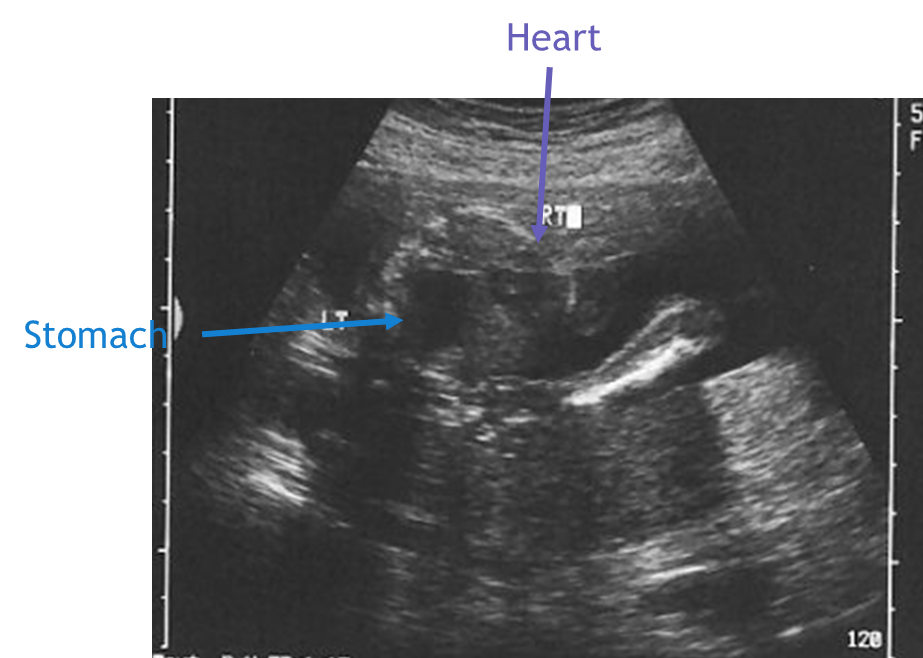

CDH